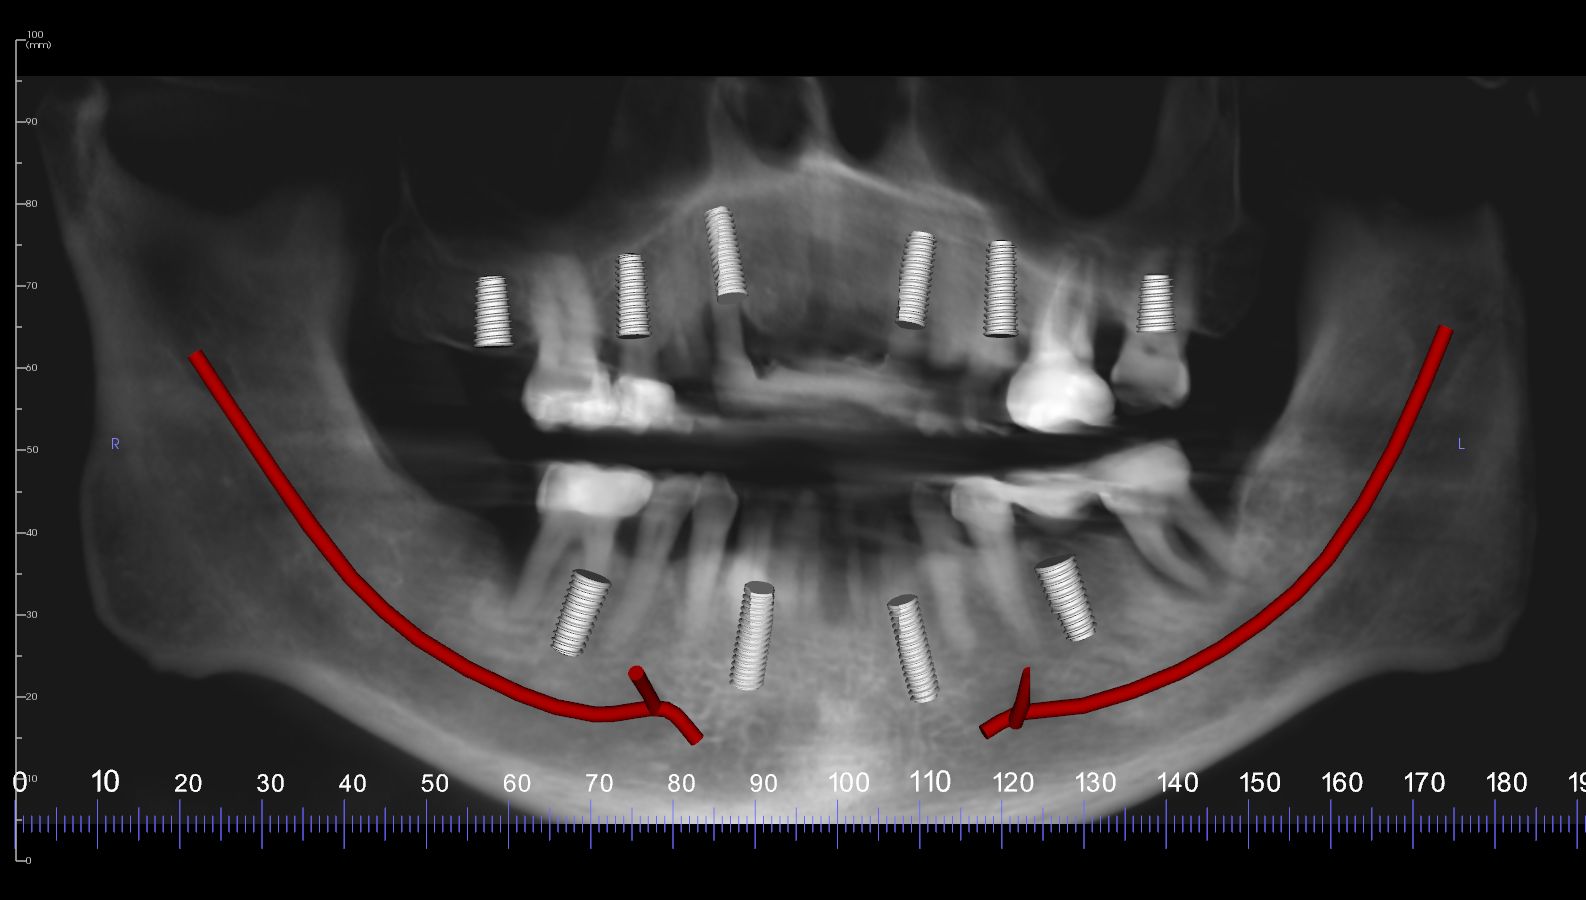

A 45-year-old man presented with a failing dentition (Figure 6). After a comprehensive analysis of his dentition, a cone beam computed tomography scan (Green CT, Vatech America) confirmed that the patient had bone quality and quantity sufficient for several different implant positions (Figure 7). Multiple treatment options were discussed with the patient, including complete dentures, implant overdentures, and fixed hybrid restorations. The patient indicated that he greatly preferred the fixed hybrid restorations, as he was not happy with the idea of removable dentition. After an extensive clinical and financial discussion, the patient concluded that fixed hybrid treatment was beyond his budget and requested implant overdenture treatment. He did inquire about the possibility of changing from the overdenture to the fixed hybrid later if his financial situation changed.

As a result of this discussion, a treatment plan of six implants on the maxillary arch and four implants on the mandibular arch was presented. The patient agreed to the treatment, and the teeth were extracted and dental implants (ET III, Hiossen) were placed in the tooth No. 2/3, 4/5, 7, 10, 13/14, 14/15 positions on the maxillary arch and the tooth No. 19, B, D, 30 positions on the mandibular arch. After osseointegration, definitive stud-style abutments (LOCATOR R-Tx) were placed and torqued according to the manufacturer's recommended torque value on implants in the maxillary and mandibular arches (Figure 8 and Figure 9).

Fig 7. A cone-beam computed tomography scan (Green CT, Vatech America) showed that the patient had an abundance of bone quality and quantity for six implants on the maxillary arch and four implants on the mandibular arch. Implants were placed in positions that would allow a fixed restoration at a later date.

Figure 7